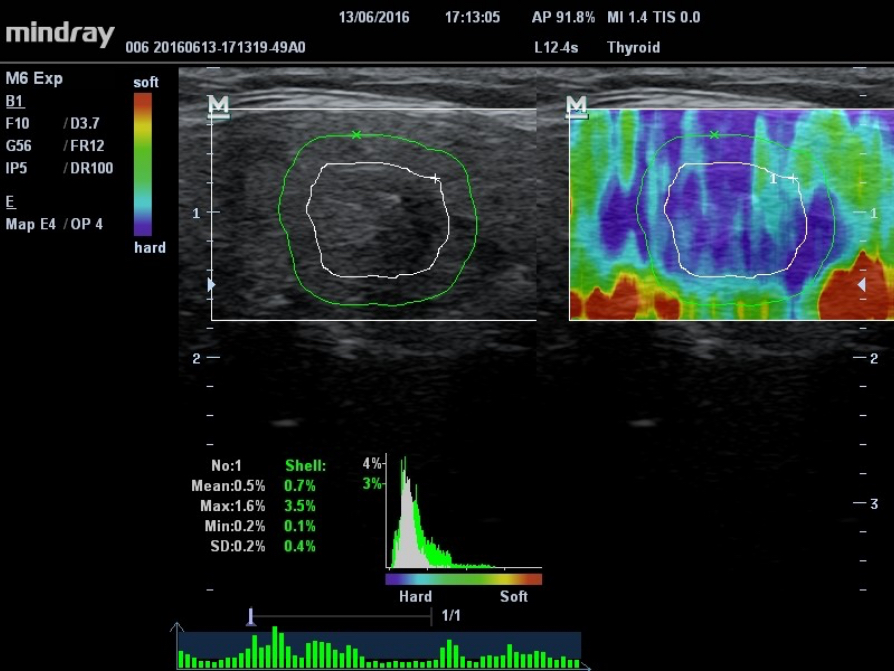

Based on MindrayŌĆÖs latest patented technology, natural touch elastography reduces dependence on user operation technique, improving operatorŌĆÖs reproducibility.

- Higher stiffness sensitivity

- Good stability and reproducibility